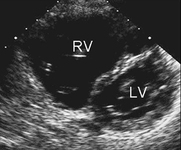

Imagen de ecocardiografía de eje corto paraesternal que demuestra agrandamiento ventricular derecho en un paciente con una comunicación interauricular (CIA). (VD) ventrículo derecho; (VI) ventrículo izquierdo

Imagen cortesía de Patrick W. O'Leary, MD